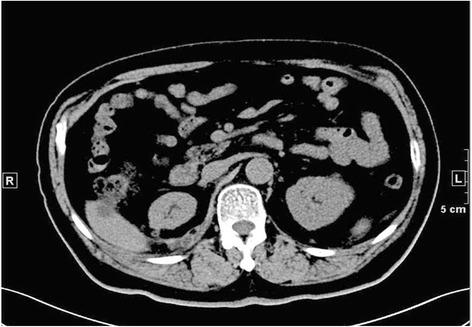

A total of 32 BSSRCC patients, including 28 males and 4 females, were enrolled the study from January 2004 to May 2016. The diagnoses were defined by the measurements of CT, ultrasound, and MRI. Patients with hereditary syndrome were excluded. The management of surgical manner, operation staging, and sequence were scheduled in accordance with the tumor's location and size (based on Zhongshan score, ZS score), as well as the performance status of the patients. Among them, 8 cases were conducted with bilateral surgical procedure simultaneously and 24 cases were implemented with staged operations. NSS on the one side with contralateral RN, and NSS on both sides were performed in 17 and 15 patients separately.

2004年1月至2016年5月,共纳入32例BSSRCC患者,其中男性28例,女性4例。通过CT、超声和MRI测量进行诊断。排除患有遗传性综合征的患者。根据肿瘤的位置和大小(基于中山评分,ZS评分)以及患者的体能状态安排手术方式、手术分期和顺序。其中,8例同时进行双侧手术,24例进行分期手术。17例患者行一侧保留肾单位手术(NSS)并对侧肾切除术(RN),15例患者行双侧NSS。